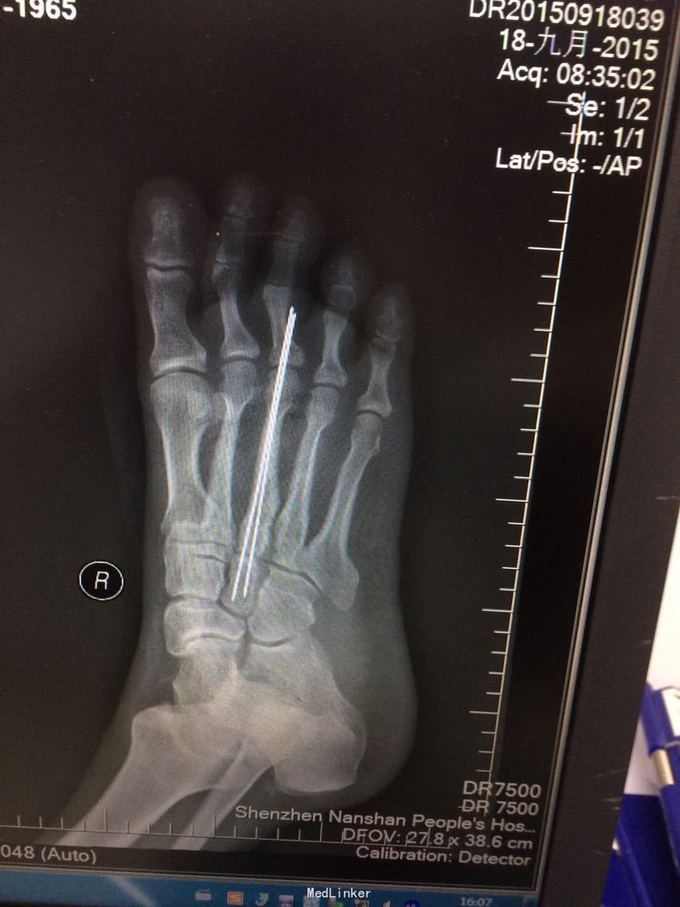

1、予石膏外固定、抬高患肢等处理,完善相关检查。 2、抗炎、活血、补液、消肿等症治疗,完善相关术前检查,择期行骨折切开复位内固定手术治疗。 3、择期行右大腿内侧取皮术+右足背游离植皮术+石膏外固定术;术后给予抗炎、消肿、补液等对症综合处理。 继续随访中现已出院待复查